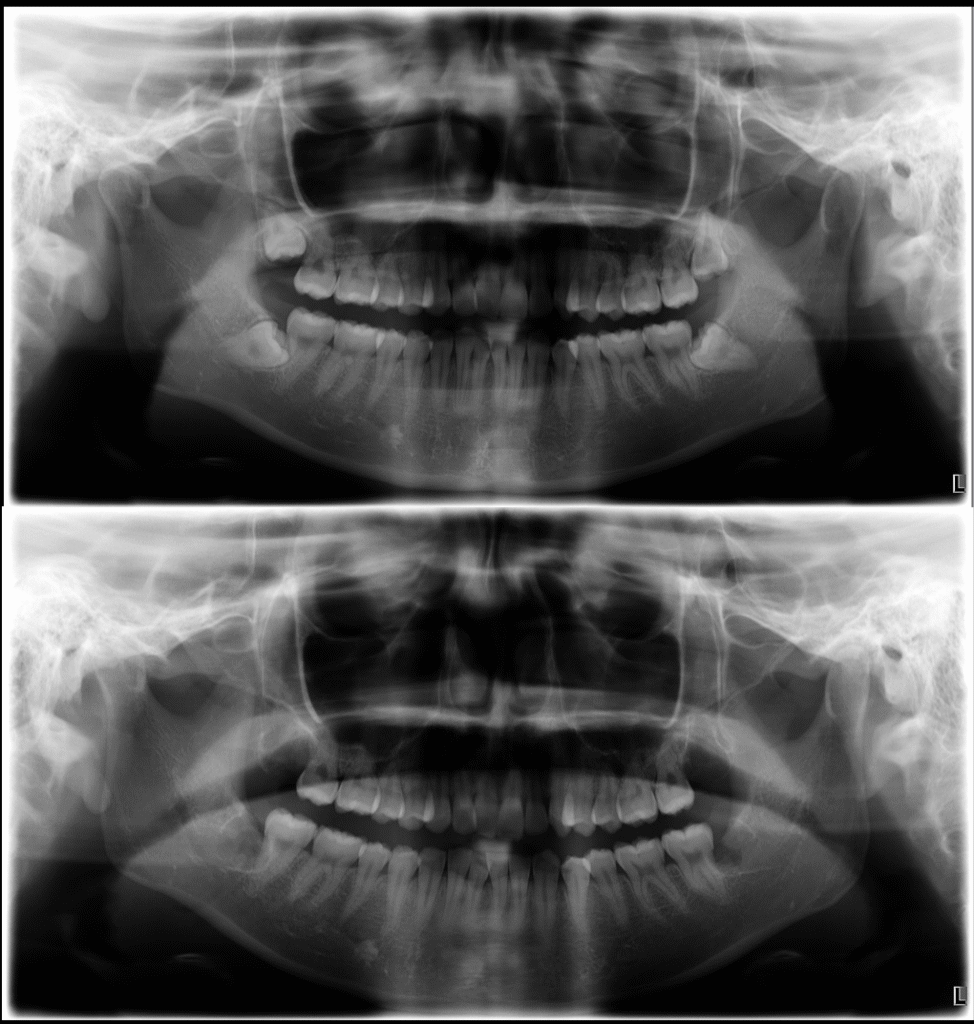

今回は、上下左右の完全埋伏智歯(4本)を同日に抜歯した20代女性の症例をもとに、

静脈内鎮静の特徴やメリットについてご紹介します。

- 静脈内鎮静下にて上下左右の完全埋伏智歯を同日抜歯

- 事前カウンセリング 親知らずの状態をCT撮影で確認し、神経や血管との位置関係を正確に診断します。